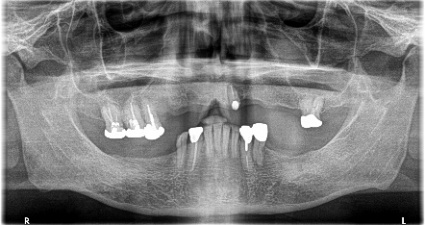

Before

※赤丸は、歯根が破折していたため抜歯しました

※黄色丸は、2006年10月に埋入したインプラント